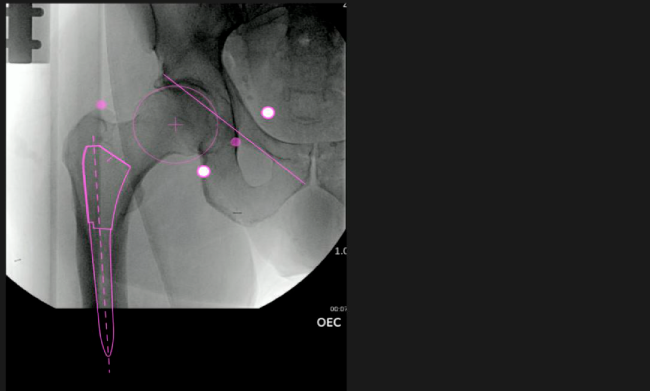

Mayor nivel de información intraoperatoria facilita la colocación correcta de los implantes:

Desplazamiento y offset para posicionamiento óptimo del componente (vástago) femoral.

Verificación de la posición deseada del implante que potencialmente puede ayudar a reducir la probabilidad de dislocación protésica y aumentar la estabilidad de la articulación.